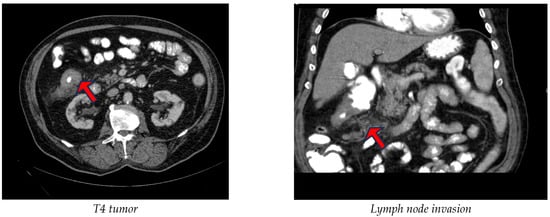

3.4. Radiological Parameters